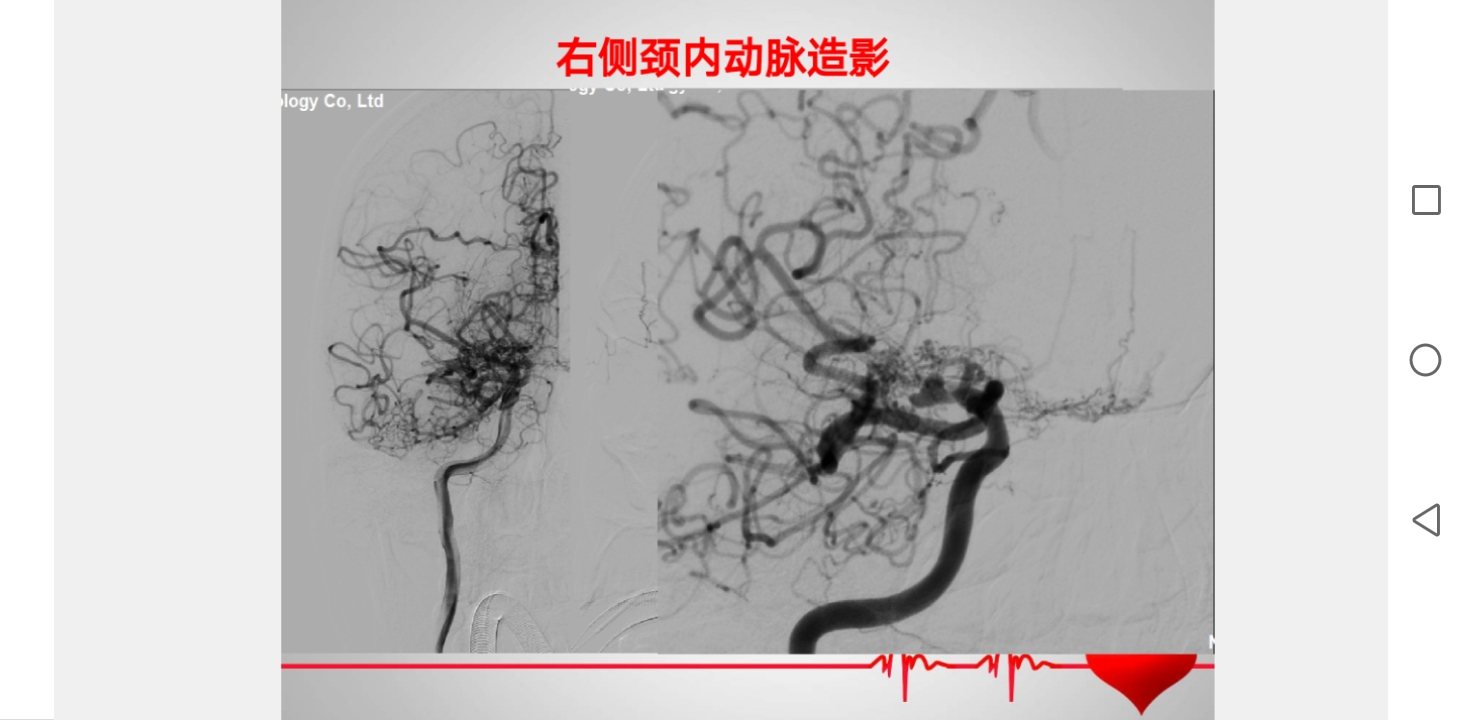

看不清动脉瘤跟血管关系,进一步脑血管造影检查,考虑右侧颈内动脉烟雾样改变,合并脉络膜前动动脉瘤